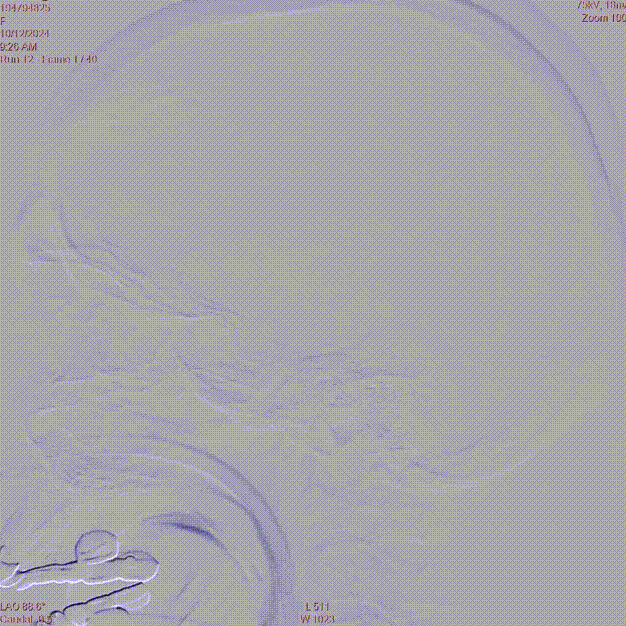

术前DSA造影(评估病变及代偿):Ⅰ型弓,左侧大脑中动脉闭塞;软脑膜动脉对其部分代偿,ASITN/SIR 1级。

术前DSA造影